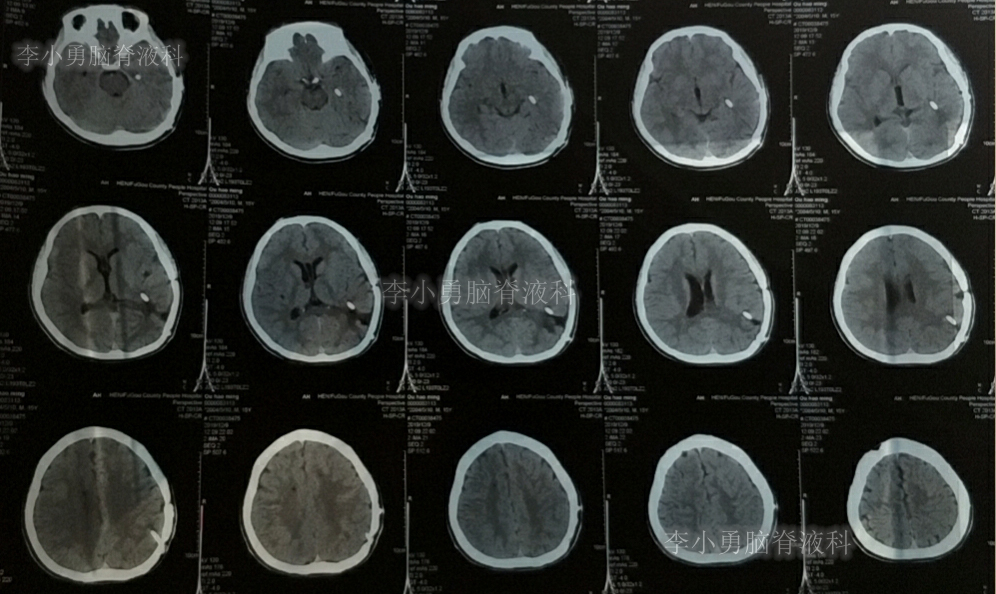

入院当日行头颅CT(图-10):脑室内“动脉瘤切除术”后改变,术区可见引流管影,脑室扩大。

图-10:2019年5月7日头颅CT:引流术后,脑室扩大

入院次日即2019年5月8日,进行了右侧脑室外引流术,并保留原来脑室外引流管(注:脑室内有两根管)。术后常规复查头颅CT(图-11)。

图-11:2019年5月9日头颅CT:引流出淡黄色脑脊液

图-12:2019年5月16日复查头颅CT:左侧颞角扩大并周边水肿

图-14:2019年5月28日头颅CT:脑室较前缩小,水肿亦减轻